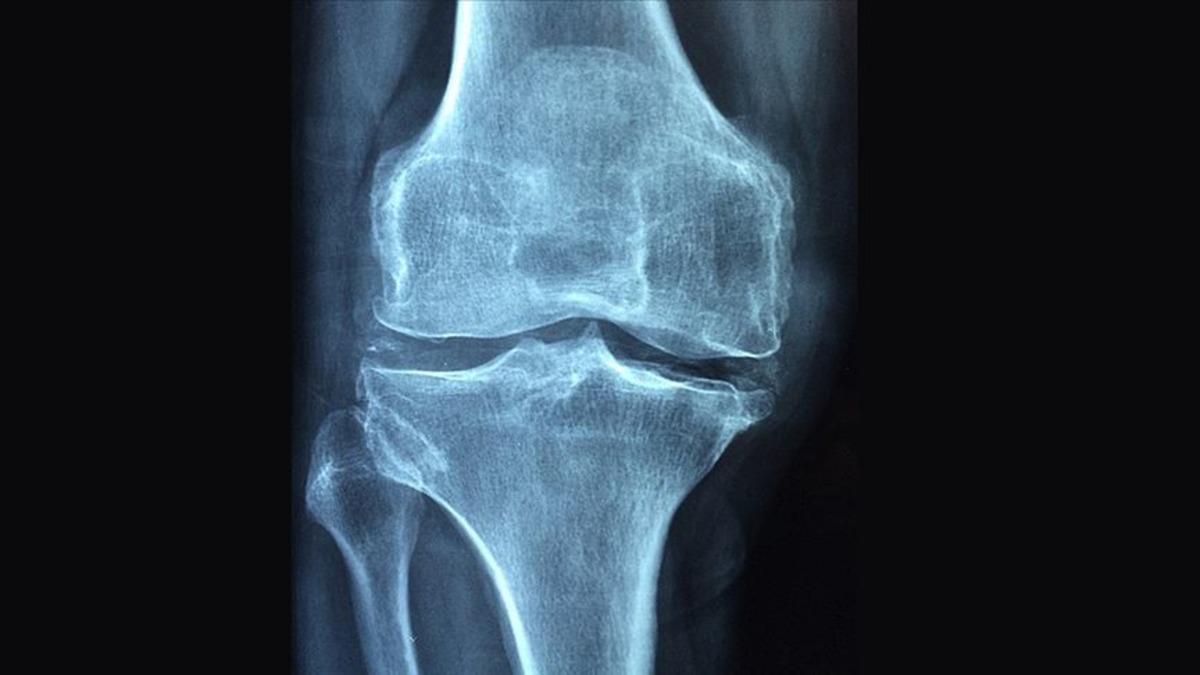

Halk arasında ‘kemik erimesi' olarak adlandırılan osteoporozu ‘kemiklerin zayıflayarak kırılgan hale gelmesi' şeklinde tanımlayan Uzm. Dr. Esra Tutal, hastalığın kemiklerin çok ufak travmalarda bile kolayca kırılmalarına neden olabildiğini söyledi. Konuyla ilgili önemli bilgiler paylaşan Uzm. Dr. Esra Tutal, osteoporozun kırık gelişine kadar hastalarda hiçbir belirti vermeyebileceğini işaret etti.

Kemik erimesine bağlı kırıkların en çok kalça, bel ve bilek kemiklerinde görüldüğünü vurgulayan Uzm. Dr. Esra Tutal, "Osteoporoz hem kadınları hem de erkekleri etkileyen bir hastalıktır. Kemik erimesi çok ileri dönemlere kadar herhangi bir belirti vermez. İleri dönemlerde ise sırt ağrısı, bel ağrısı, boyun zamanla kısalması ve duruş bozukluğu (kamburluk) meydana gelir" dedi.

İnsan vücudunda kemik yapım ve yıkımının belli bir denge içerisinde olduğunun altını çizen Uzm. Dr. Esra Tutal, "20 yaşına kadar kemik yapımı ön plandadır. 30 yaşına kadar maksimum kemik kitlesi oluşur. 30 yaşından sonra ise yıkım ön plana geçer. Maksimum kemik kitlesi ne kadar iyi ise vücut yıkımdan o kadar az etkilenir. Kadınlar, yaşlılar, ailesinde kırık öyküsü olanlar ve zayıf minyon yapılı olanlarda daha sık görülür.